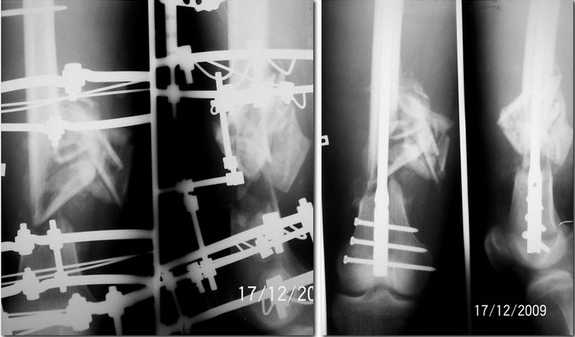

Николов Олег 18 Декабрь 2009, 01:41

Прислушавшись к мнению уважаемых коллег провели двухэтапное лечение пациента. Пару дней

назад забили штифт, без укорочения, колено редрессировали до 90гр. Всем спасибо за дельные

советы.

Уважаемые коллеги! Очень демонстративный и профессионально проведенный остеосинтез. Удачи, так держать! С уважением Ерсин Жунусов.

Поздравляю, очень симпатично получилось.